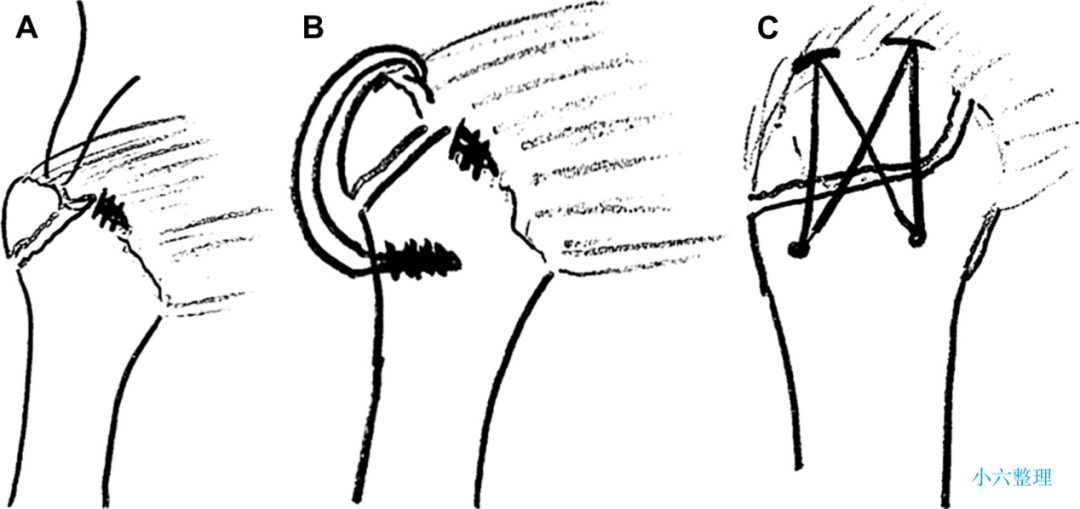

目前常用的外科技术

肱骨大结节骨折 ORIF,术前 X 线片显示肱骨大结节骨折情况;术中暴露肱

肱骨大结节骨折 ORIF,术前 X 线片显示肱骨大结节骨折情况;术中暴露肱